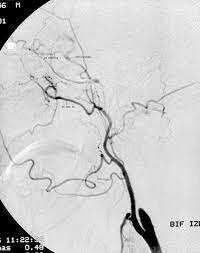

Demostración de la oclusión carotidea

En 1941, se demostró hagiográficamente la oclusión carotidea en pacientes con déficit motor.